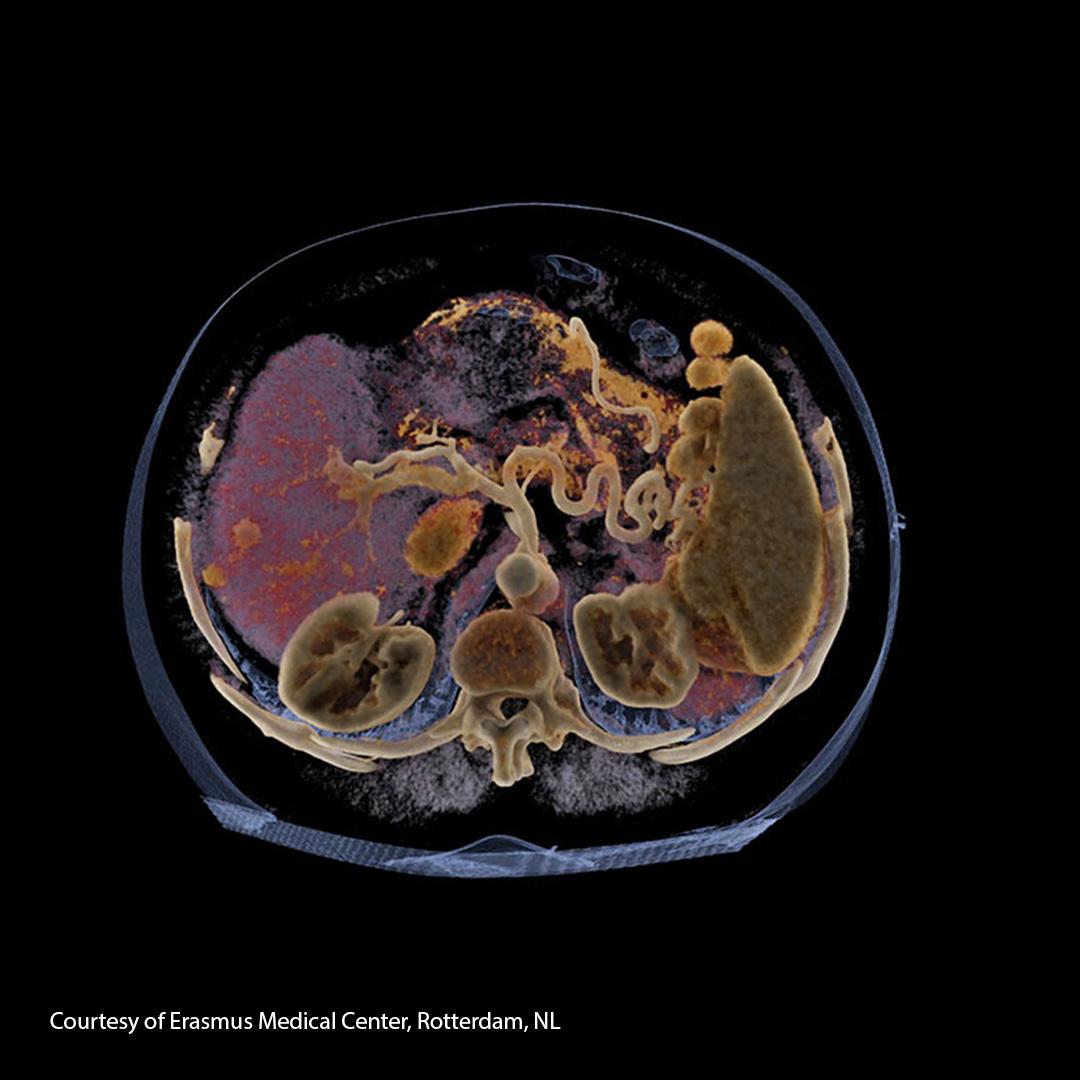

By contrast, diagnosing liver cancer requires a physical examination and special medical tests. Diagnosis of hepatocellular carcinoma (HCC) is done using imaging tools like ultrasound, computed tomography (CT), or magnetic resonance imaging (MRI) and in many cases doesn’t even require biopsy.

Siemens Healthineers provides imaging technology and the smart imaging value chain that enable reliable therapy decisions. Sometimes a liver biopsy is performed to confirm the diagnosis of liver cancer. Genetic testing of the cancer can help determine the best type of treatment for the patient.